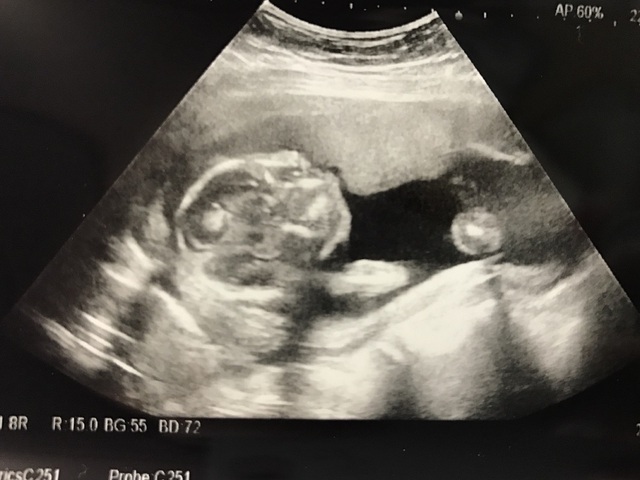

19週5日(19w5d・男の子)|グースケ さん(34歳)

エコー写真撮影時のエピソード:

里帰り出産にする予定で、実家の方の病院を受診した時に双子だと初めてわかりました。ビックリと同時に、二人とも元気で生まれてほしいと願っています。

双子は色々リスクがあるらしく、受診してエコーを撮るたびに二人が同じ様に成長してくれているかとても気になります。